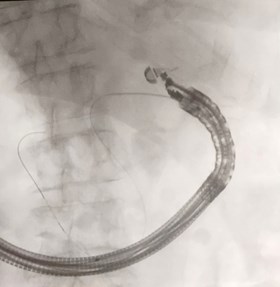

Accesso ecoendoguidato nella via biliare principale

Gastroenterologia ed endoscopia digestiva, eseguito innovativo intervento

Tecnica di "rendez-vous" per la rimozione “difficile” di un calcolo